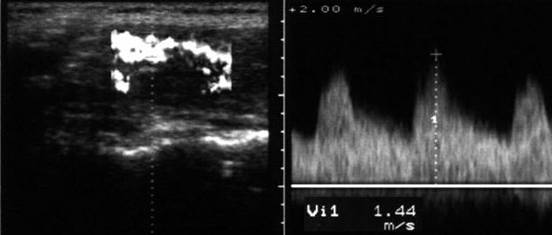

Examen doppler cu calcul al al velocitatii instantanee a arterelor tiroidiene

superioare.

De notat cresterea velocitatii (0,60 m/s).